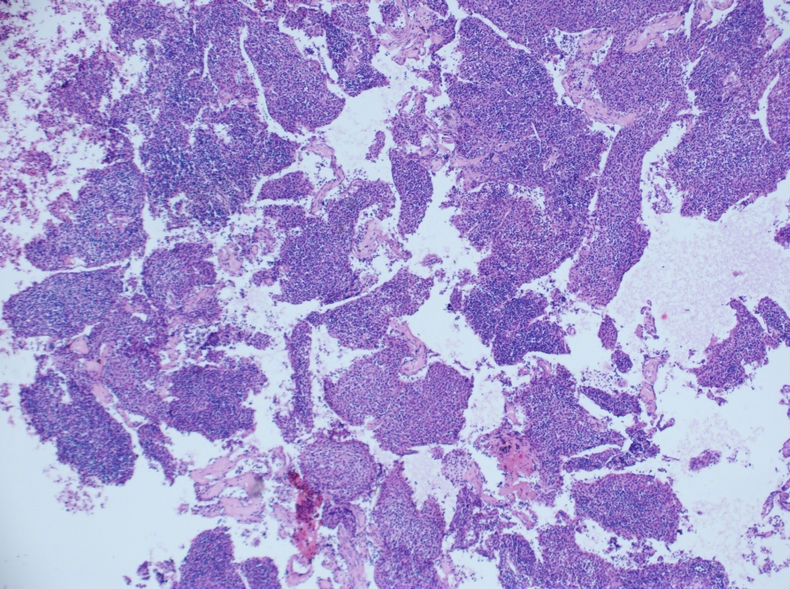

发现左侧胸壁肋间肿块1月,约3.5×4 。病例分享——男性,55岁,左胸壁肋间肿块图1

肋间肿块切除的标本有的,形态和细胞腊块一致,属于胸腺瘤B2+B3型。

根据腊块及免疫组化结果,我诊断了

(左胸壁)转移性胸腺瘤(B2型)

建议检查纵隔。

随访,纵隔发现一3.5×3cm肿块,术后病理示:胸腺瘤(B3型为主)

我当时就让病人等两天,等我把细胞腊块的结果出来后告诉他。

细胞腊块图片如下:

的确这例涂片诊断非常困难,我刚看到涂片的时候,也是一团雾水,我看到淋巴细胞及组织细胞样细胞两种成分。

当时考虑:1、肉芽肿性炎,2、转移性鼻咽部的非角化性未分化癌、3、淋巴结增生、4、转移性胸腺瘤,5、软组织肿瘤6、……

反正良恶性我分不清。